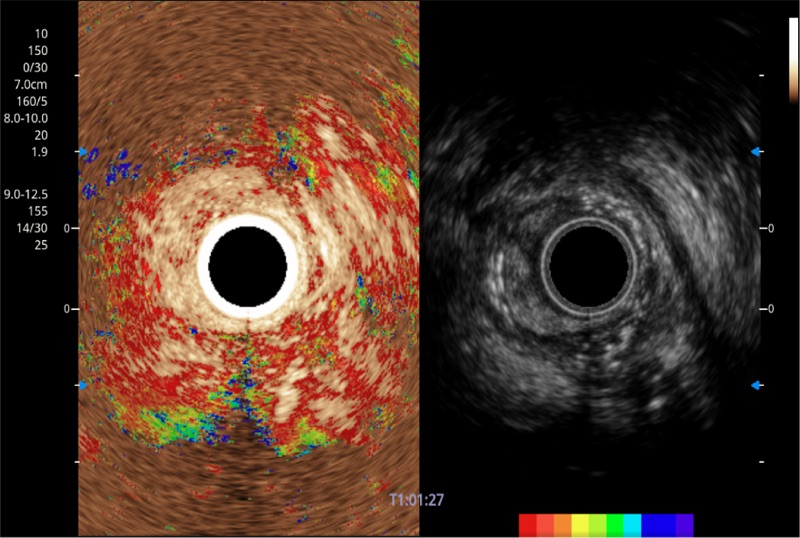

可人为将灰阶图像转变成彩色的显示方式,增强人眼对于不同回声强度的敏感度,主观上增加了图像分辨率

微米成像技术提升了对组织斑点噪声信号的抑制能力,并进一步强化边界信息,从而获得信噪比更优、边界更清楚锐利的图像

随着组织深度的变化,超声接收频率进行智能匹配跟踪,确保图像中、远场良好的穿透力以及整场一致的分辨力,从而得到均一的画质

肝左叶和肝静脉的横截面